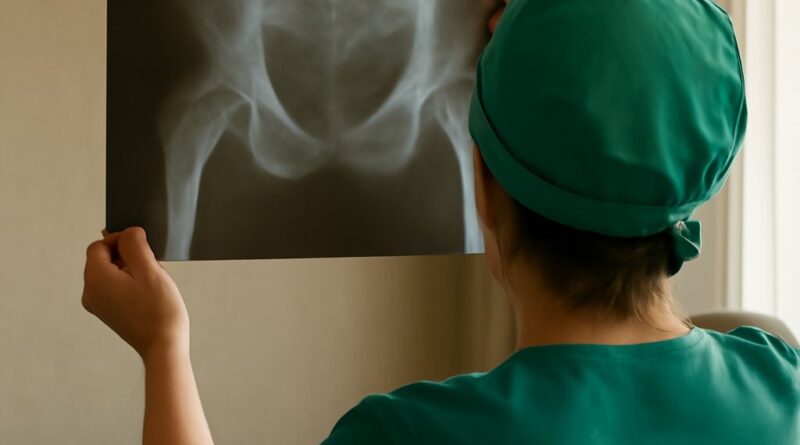

Read MoreSpine MRI: What the Scan Shows, Equipment Used, and Average Cost Without Insurance A spine MRI is one of the